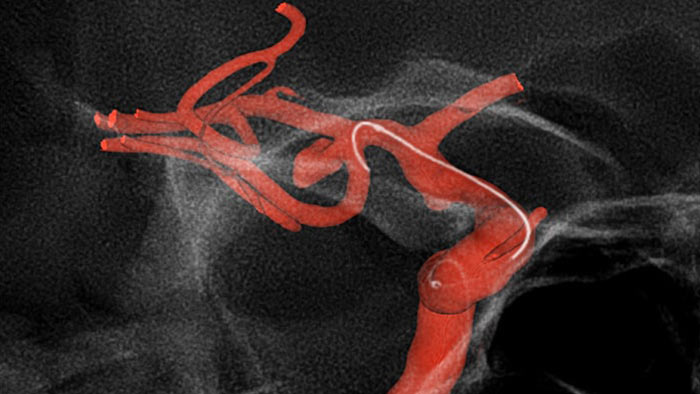

O Roteiro do SmartCT aprimora a visualização de vasos sobrepostos para facilitar a navegação precisa do fio guia e do cateter ao longo de uma vasculatura complexa. Oferece precisão de alto nível com compensação em tempo real para movimentos do gantry e da mesa e pequenos movimentos do paciente.